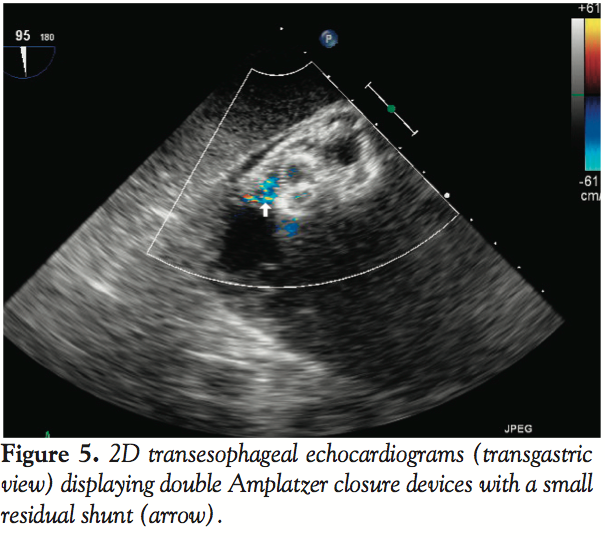

A 16 mm VSD Amplatzer occluder device (AGA Medical) was deployed across the VSD in the standard technique under fluoroscopic and echocardiographic (2D and 3D) guidance through a 9 Fr x 180 cm TorqVue delivery system (AGA Medical) placed in the right internal jugular vein. The first device was inserted via a left ventricular approach with release from the delivery cable and was anchored in the surrounding tissue. After deployment, TEE revealed significant residual shunting with color-flow disturbance and a VSD measuring 0.5 cm in

length in another echocardiographic plane of the interventricular septum. The VSD was determined to possess a unique serpiginous, S-shaped anatomy with adjacent aneurysm. We decided to deploy a second Amplatzer occluder (12 mm) in order to address the residual VSD. The second device was placed adjacent to the first occluder and appeared to be parallel when interrogated with 3D TEE (Figure 4). Color Doppler 2D TEE showed a very small residual VSD (Figure 5); left ventricular size was normal and left ventricular function was preserved.